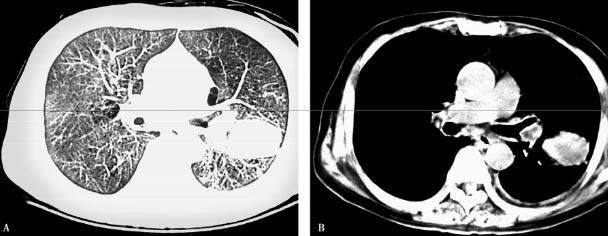

6.胸部CT:双肺下叶、右肺上叶可见斑片状高密度影,左肺可见团块状高密度影,分界不清,CT值20HU。

根据检查结果回报:①末梢血白细胞计数、中性粒细胞百分比及CRP均明显增高;②肺功能示重度阻塞性通气功能障碍,支气管舒张试验阴性;胸部影像学示双肺炎性改变,左肺可见团块状高密度影,分界不清,CT值20HU。;结合患者的病史和体格检查结果,考虑为感染所致慢性阻塞性肺疾病急性加重、左肺下叶占位性病变,目前病原学尚不明确,患者发病以来未系统用药治疗,病史长,反复发作,肺功能示重度阻塞性通气功能障碍,双肺炎性改变,说明患者慢性阻塞性肺疾病病情重,加之此次感染,炎症已累及多肺叶,通气功能进行性下降,患者自觉呼吸困难。进一步的处理应是立即选择合适的抗感染药物进行治疗,同时进一步完善肺部肿瘤相关检查,治疗感染的同时,进一步明确诊断。

经哌拉西林钠/他唑巴坦钠坦抗感染治疗体温较前降低,咳嗽咳痰及呼吸困难症状较前有所缓解,双肺啰音较前减少,患者左胸部疼痛,自觉与呼吸相关。在此期间实验室检查结果:①血常规白细胞总数及中性粒细胞百分比较前下降;②血清各种抗体(支原体、衣原体、军团菌)仍阴性;③痰菌培养:肺炎克雷伯杆菌(3次);④胸部CT:双肺斑片状高密度影较前略有吸收,但左肺团块影仍存在(图1A肺窗、B纵隔窗)。

图1

(二)临床分析

给予患者初始经验治疗后,综合评估肺部炎症较前缓解,但有胸痛且与呼吸相关,考虑与肺部病灶累及胸膜有关,或与其他因素,如肺部占位病变有关,应进一步完善肿瘤相关化验检查,肿瘤病理检查,明确病灶性质,同时可评估患者是否存在胸骨转移导致患者胸痛。还应继续询问患者病史,以掌握更多的临床证据。